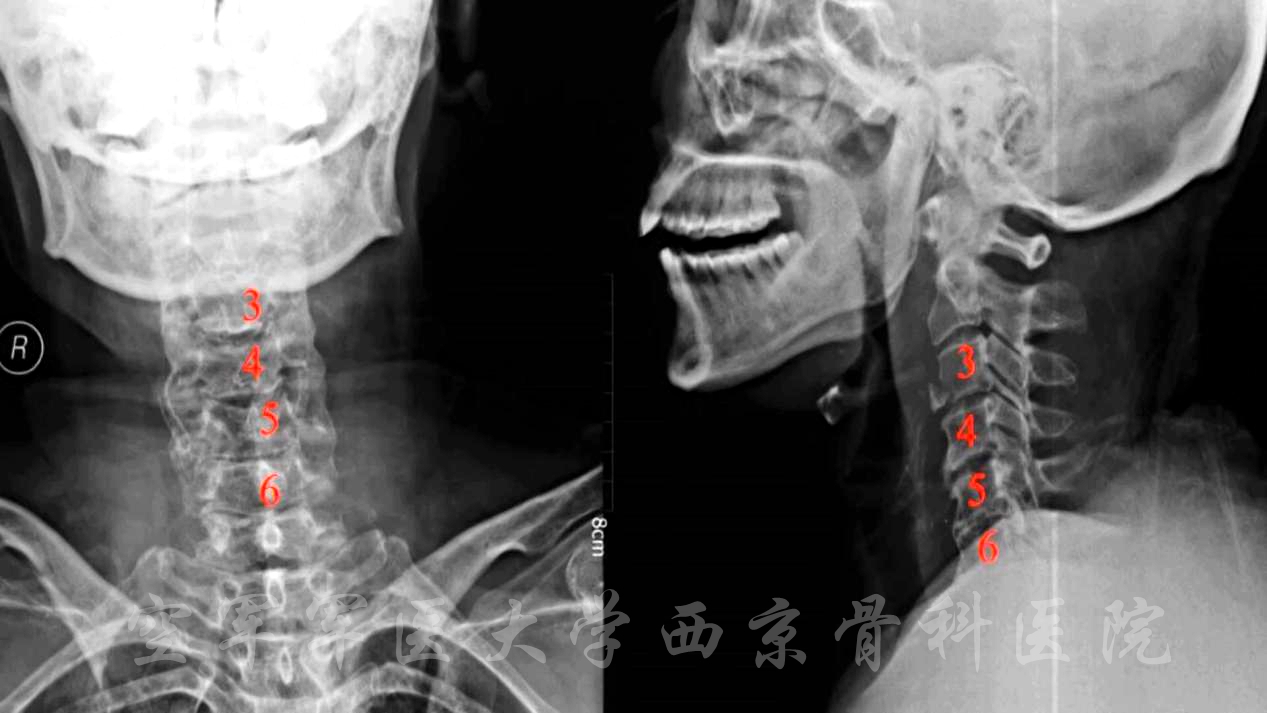

颈椎后路椎板切除减压,C3-6侧块螺钉、C2椎弓根螺钉固定,植骨融合手术

患者:女,60岁

主诉:外伤致颈痛伴双上肢活动不能10小时。

现病史:患者因10小时前车祸致伤。

查体:

平车推入病房,颈托固定。锁骨以下躯体感觉减退,左上肢为著。三角肌左/右=0/Ⅰ级,肱二头肌左/右=Ⅰ/Ⅱ级,腕伸肌左/右=Ⅰ/Ⅱ级,肱三头肌左/右=Ⅰ/Ⅱ级,指深浅屈肌左/右=Ⅰ/Ⅱ级,小指展肌左/右=Ⅰ/Ⅱ级,双下肢肌力约Ⅳ级。四肢腱反射未引出,双侧病理反射未引出。

诊断:

1.颈3椎体骨折并不全瘫;

2.颈椎后纵韧带骨化;

3.高血压病2级。

术前X线正侧位片